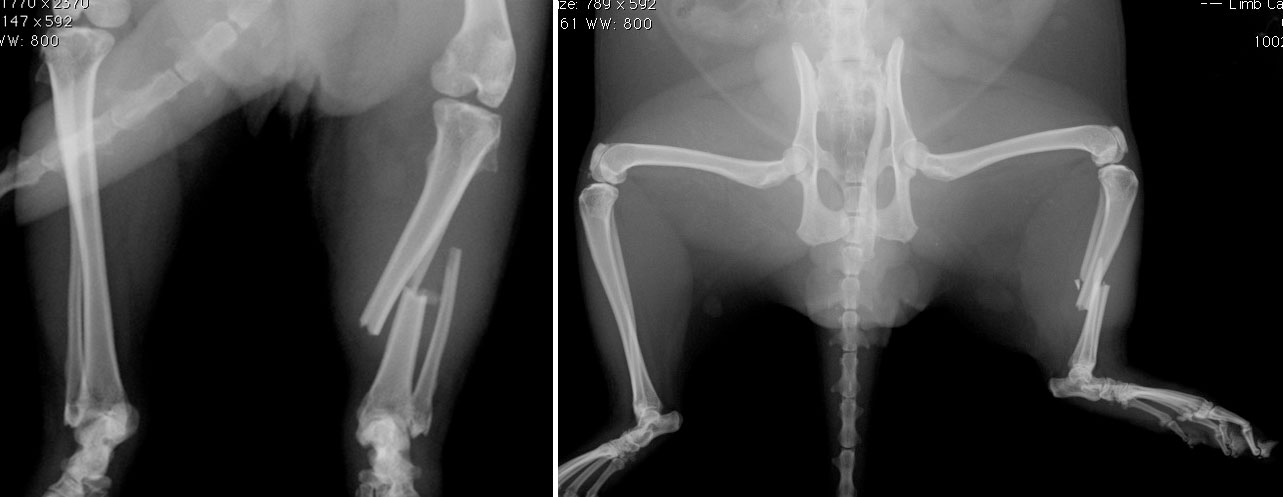

Jack Daniels (JD) is a ferret who came to see us in September with a very lame leg.

We x-rayed him and found that unfortunately he had broken his leg.

This presented us with quite the challenge because JD’s bones were so tiny. I performed an extremely fiddly operation to fix his bones back together again. Below you can see the x-rays we took after the operation - the white lines are tiny 1mm wide pins that are holding the two ends of bone together whilst the body heals them. The operation went extremely well and JD should make a full recovery.